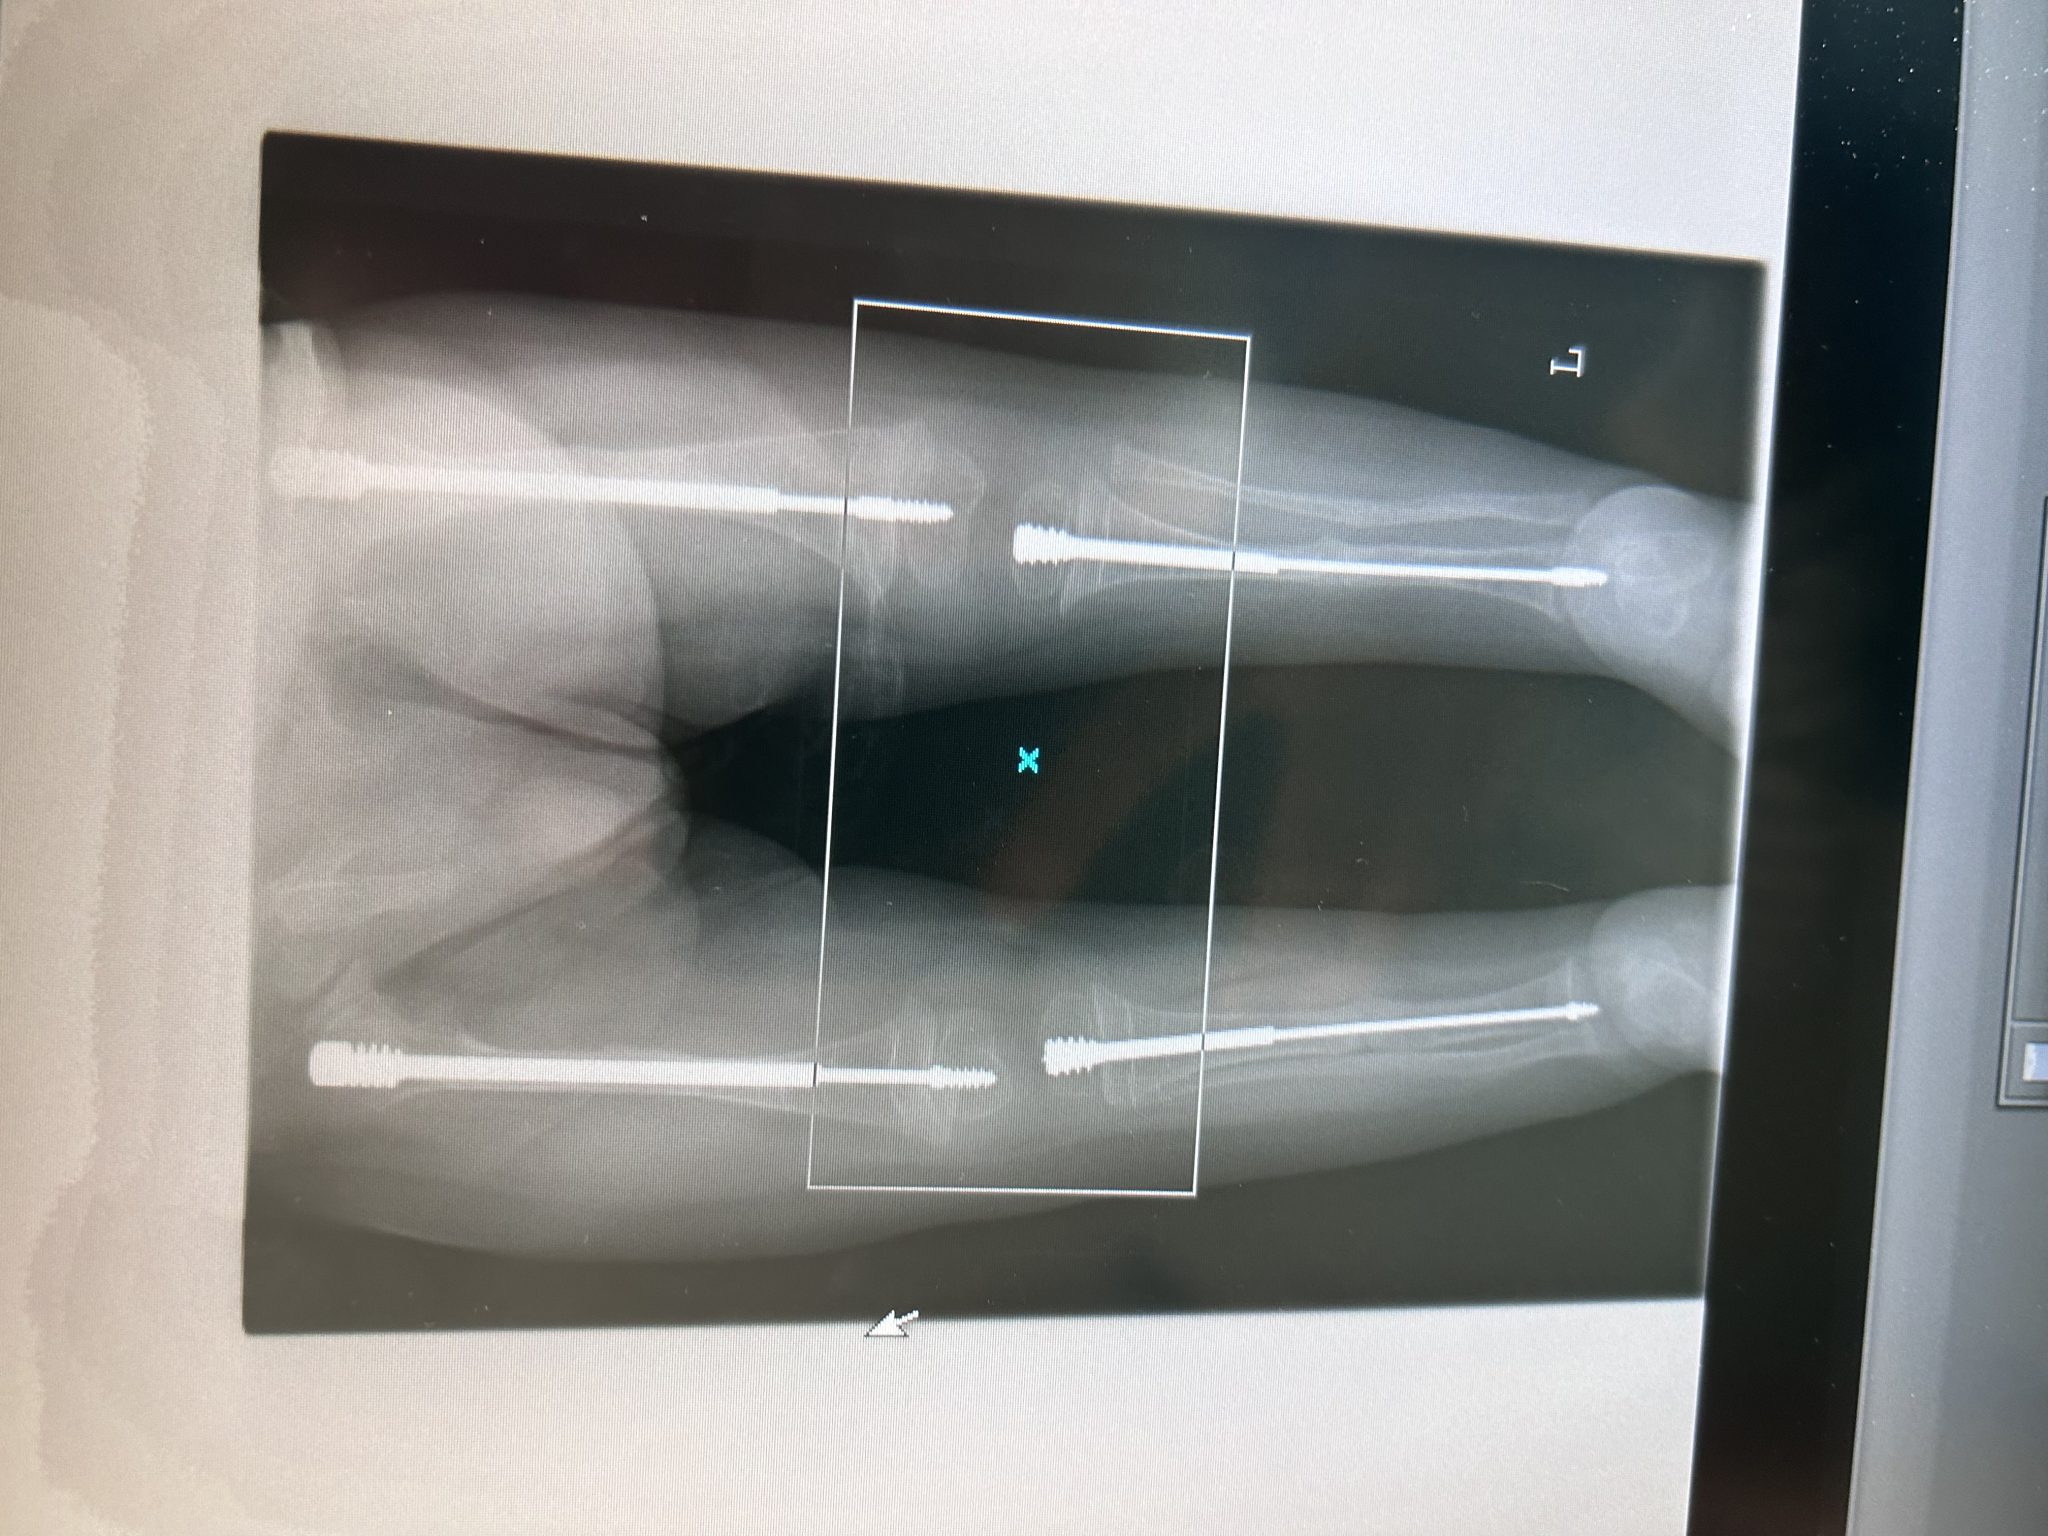

Mam na imię Franek, urodziłem się 3 listopada 2022 roku. Dzień, w którym moi rodzice dowiedzieli się o mnie, był najszczęśliwszym dniem w ich Każdy dzień w oczekiwaniu na moje pojawienie się na tym świecie, był przepełniony wielką miłością oraz radością. Niestety, 27 lipca cały nasz świat wywrócił się do góry nogami. Kontrolne badanie USG zmieniło wszystko… Padło podejrzenie WRODZONEJ ŁAMLIWOŚCI KOŚCI. Od tej pory każdy dzień moich rodziców, przepełniony był strachem o to, co będzie. Już w brzuchu mojej mamy doznałem kilku złamań, co spowodowało łukowate wygięcie moich kończyn – głównie nóżek, co tuż po urodzeniu potwierdziło diagnozę. Jedyną szansą na moje lepsze jutro są intensywne rehabilitacje, częste konsultacje u wielu specjalistów oraz skomplikowane operacje chirurgiczne polegające na wzmocnieniu moich słabych kości specjalistycznymi prętami. Do tej pory przeszedłem już aż 4 operację, a to nadal nie jest koniec… Jestem na długiej i trudnej drodze do lepszej przyszłości, ale wierzę, że z Waszą pomocą przejdę przez nią z uśmiechem na twarzy.